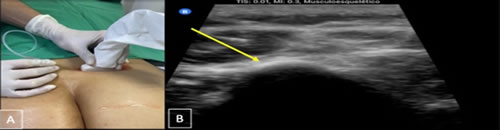

Métodos: Estudio de tipo observacional, retrospectivo, realizado en pacientes diagnosticados con dolor lumbar crónico y signos y síntomas de atrapamiento de nervios cluneales o clunealgía llevados a bloqueo de nervios cluneales en quienes que se evaluó la intensidad del dolor y duración del efecto analgésico en cuatro momentos.

Methods: Observational, retrospective study, carried out in patients diagnosed with chronic low back pain and signs and symptoms of cluneal nerve entrapment or clunealgia leading to cluneal nerve block in whom pain intensity and duration of the analgesic effect were evaluated in four moments.

10.	Chang KV, Hsu SH, Wu WT, Özçakar L. Ultrasonographic Technique for Imaging and Injecting the Superior Cluneal Nerve. Am J Phys Med Rehabil. 2017;96(6):e117-e118.